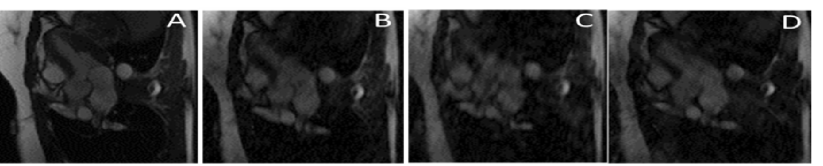

The favorable performance of our method is also shown in Figure LABEL:fig:comp. Compared to PILOT’s reconstruction, Multi-PILOT exhibits significantly less imaging noise and artifacts. The corresponding acquisition trajectories and correlation with visual results are further explained in Appendix LABEL:fig:withtrajs. Additional visual results are presented in Appendix A.1.

We also present a more detailed explanation of LABEL:fig:comp.

fig:withtrajs

Figure LABEL:fig:withtrajs shows the trajectories used to acquire the corresponding frames from LABEL:fig:comp. Many of the data in each frame is encapsulated at the center of the -space. The learned trajectories show that while PILOT’s single trajectory must allocate many acquisition points for capturing central frequencies, the Multi-PILOT trajectory can afford using trajectories more spread around the -space, as data represented using the center frequencies are also captured by other frames. MultiPILOT does better in reconstructing the finer details compared to GAR initialization and PILOT reconstruction.